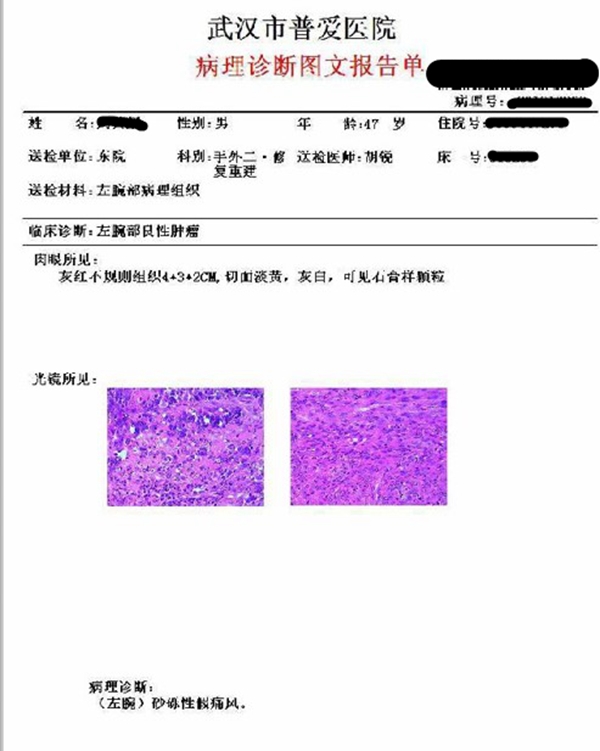

术后病理

图4.膜组织内见多灶、团块状紫蓝色钙化结晶体沉积